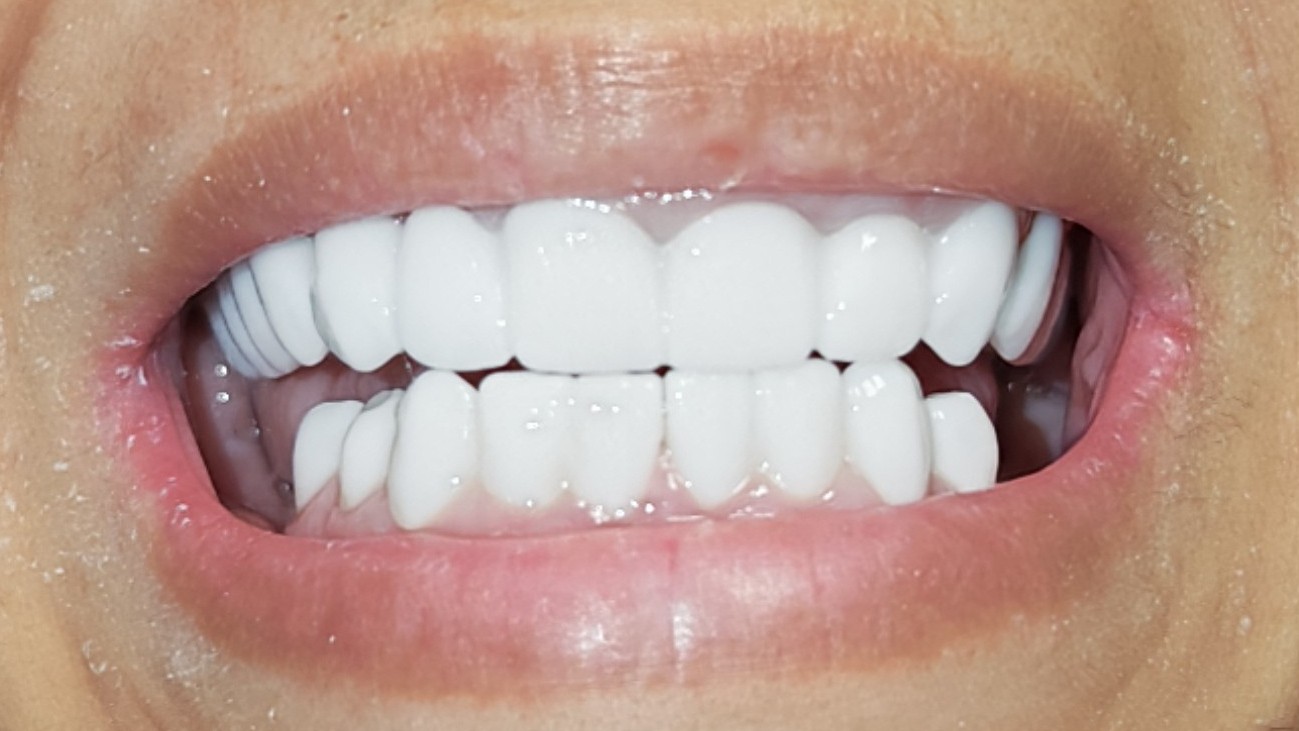

Coroane Zirconiu - pacient cu defect muscatura lipsa cronica molari

Coroane Zirconiu